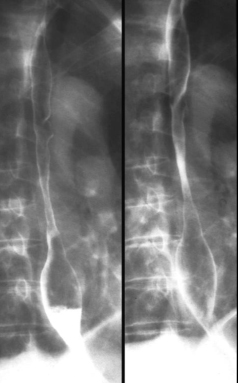

Oesophagite caustique

: Correspond a une inflamation de la muqueuse

oesophagien par ingestion acidentellement ou volontaire du

liquide caustique par exanple soude ou acide . Evolution de

cette type d'infection c'est la perdre l'elasticite de

paroie de oesophage . Image radiologique TOGD de cette type

oesophagite est image stenose cicatricielle etendue de

oesophage :

Image radiologique du transit

oesophagien d'un oesophagite caustique . C'est image

de stenose cicatricielle tres etendu de 2/3

inferierure oesophage |

|

Une autre cas de

oesophagite caustique . La lesion etendue le long

2/3 superiere de oesophage . Image radiologique du

transit oesophagien en OAD |

Oesophagite caustique 1/3 moyen de

oesophage avec aspect lesionaire c'est imsage

stenose cicatricielle a bord lisse de perdre

elasticite ( fleche blanche ) |